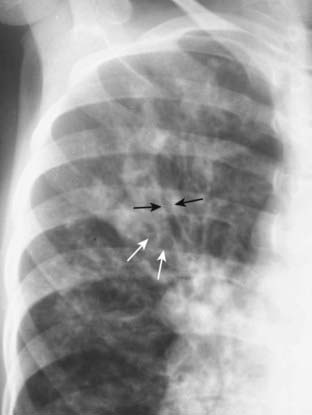

Figure 12-22 Types of emphysema.

A, Centriacinar (centrilobular) emphysema features focal destruction limited to the respiratory bronchioles and the central portions of the acinus (solid white arrows). It is associated with cigarette smoking and is most severe in the upper lobes. B, Panacinar (panlobular) emphysema involves the entire alveolus distal to the terminal bronchiole, is most severe in the lower lung zones, and generally develops in patients with homozygous alpha1-antitrypsin deficiency. C, Paraseptal emphysema is the least common form, involves distal airway structures, alveolar ducts, and sacs, tends to be subpleural, and may cause pneumothorax.